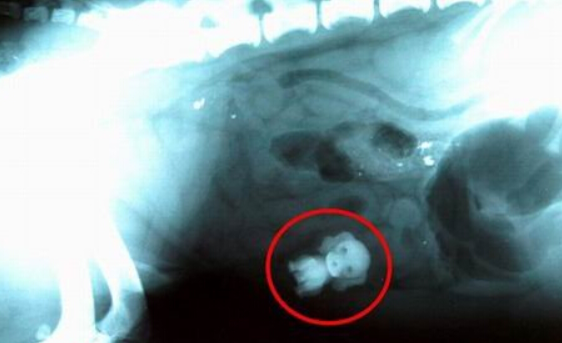

经兽医X光扫描显示,一只斯班尼犬胃中有一个玩具狗

当兽医对它进行X光扫描时,发现它的胃中竟有一只玩具狗,达顿猜测很可能是这条斯班尼犬趁女儿不在时,偷偷地进入她的房间,并将这个玩具狗吞入口中。兽医马克-阿灵顿(Mark Allington)说:“我们进行X光扫描时,很显然地看到它的胃中有一只玩具狗,经过两个小时的手术,才将玩具狗取出来。”